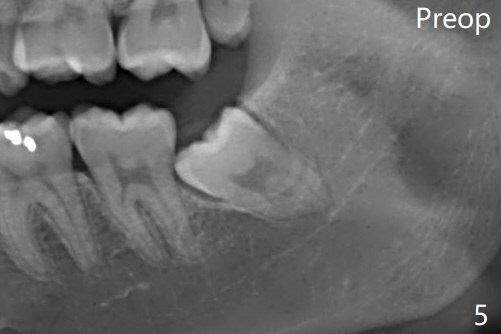

Osteogen plug was placed in #17 socket 1 year ago.

Buccal Impaction Last Next